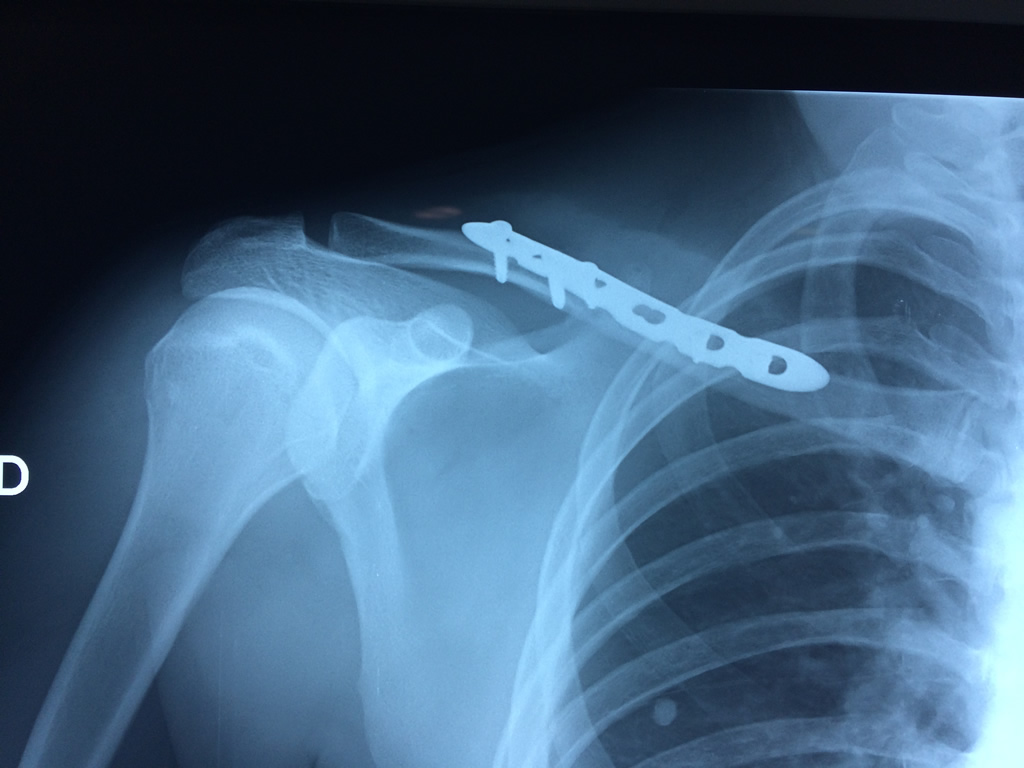

Húmero - Clavícula